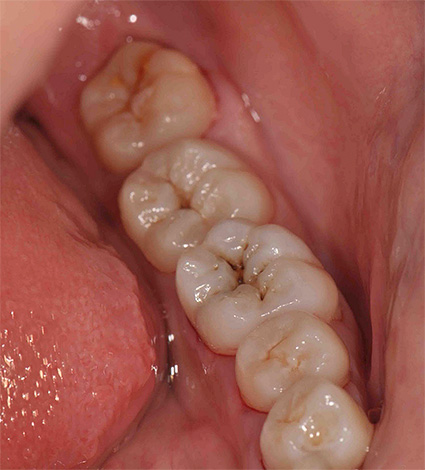

La carie delle fessure colpisce principalmente le aree più deboli sulla superficie masticatoria dei denti posteriori. Molto spesso, la patologia si sviluppa nei bambini sui primi molari permanenti (sul sesto dente).

Lo sviluppo della carie delle fessure nei primi molari permanenti è dovuto al fatto che questi denti eruttano in un bambino già di 6 anni. La loro dentizione spesso rimane inosservata dai genitori e talvolta viene erroneamente considerata come l'aspetto del latte (denti temporanei), che cadrà comunque.

Molto spesso, il sesto dente inferiore erutta inizialmente e i denti superiori solo dopo un po ', quindi l'autopulizia non si verifica durante la masticazione, poiché non ci sono aree di contatto. Un bambino non può garantire da solo la corretta igiene di tali siti posteriori così distanti, di conseguenza, sorge una sorta di "rifiuto biologico". Le fessure costantemente contaminate da residui di carboidrati iniziano a scurirsi, perché sotto l'azione degli acidi organici, zone di demineralizzazione (un contenuto ridotto di minerali nel reticolo cristallino dello smalto) sorgono sotto gli strati superficiali dello smalto.